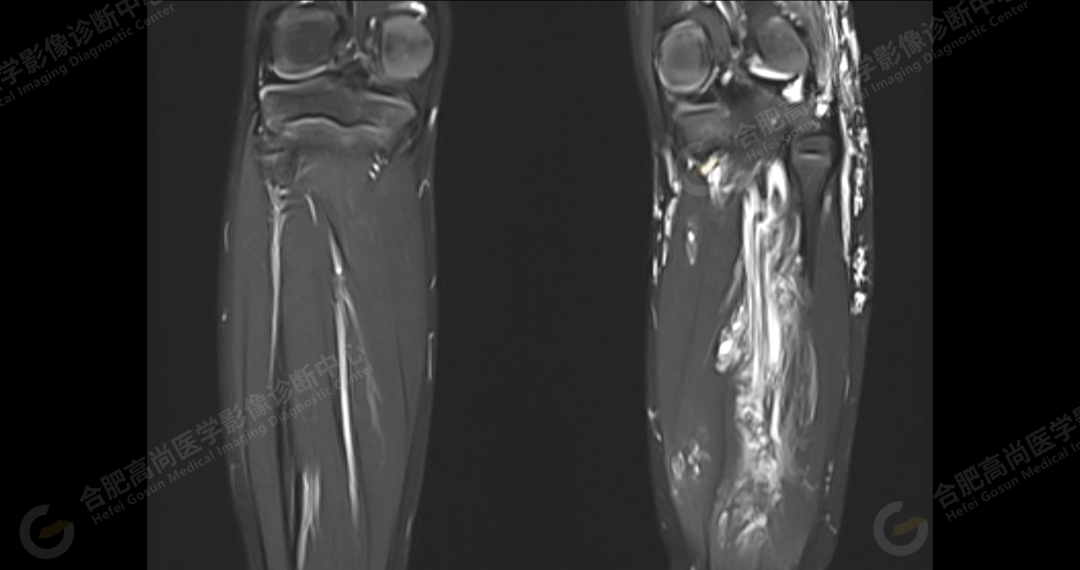

左侧髂骨内侧及闭孔内肌前方可见网格状异常信号影,边界欠清,T1WI 呈低信号,T2 压脂呈高信号,病变连续,延伸至臀肌内;左侧臀肌间隙及皮下、左大腿后部肌肉群及皮下、左膝前外侧及腘窝皮下、左小腿后侧皮下累及比目鱼肌及内外侧腓肠肌、左内外踝皮下、左足背足底及左足肌间隙内可见大片状、结节状弥漫性异常信号影,形态不规则,分布不均匀,边界不清,T1WI 呈低信号,T2WI 压脂后病灶呈高信号,部分病灶内可见网格状低信号,左足部肌间隙增宽,第 2-4 跖骨稍受压,骨质结构完整。左髋关节、膝、左踝关节间隙正常,无明显狭窄及增宽,关节面光滑,关节腔内无积液,左股骨、胫腓骨及踝部各组成骨骨质结构完整,未见明显异常改变。

左侧盆腔及下肢皮下及部分肌间隙内漫状血管瘤,请结合临床。